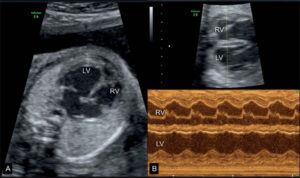

При выполнении ЭхоКГ используются различные режимы сканирования, позволяющие детально визуализировать сердце плода:

- двухмерная эхокардиография – используется для оценки анатомии основных структур сердца (камер, клапанов, главных артерий и вен). Изображение выводится в виде двухмерного среза.

- М-эхокардиография – позволяет наблюдать интракардиальные структуры (стенки камер сердца, створки клапанов) в режиме движения, оценивать систолическую функцию желудочков.

- Допплерэхокардиография – используется для изучения гемодинамики в сосудах и камерах сердца, а также оценки сердечного ритма. Проводится в режиме ЦДК и импульсной допплерографии.

Стандартное эхографическое исследование включает оценку четырехкамерного среза сердца (положения сердца в грудной полости, строения желудочков и предсердий, сформированности межжелудочковой и межпредсердной перегородок, движений створок митрального и трикуспидального клапанов), главных артерий (взаиморасположение и диаметр аорты и легочного ствола), характеристик сердечной деятельности (ЧСС, ритмичности предсердно-желудочковых сокращений). С протоколом эхокардиографии плода в обязательном порядке должен быть ознакомлен акушер-гинеколог, наблюдающий беременность, который прокомментирует женщине результаты диагностики, объяснит все имеющиеся риски.

Во втором триместре УЗИ наиболее информативно с 18 по 28 недели, как раз когда проводится второй скрининг, но оптимально в 24. К этому времени можно максимально полно рассмотреть структуры, заметить нарушение ритма. Сердце на мониторе крупного размера и занимает третью часть грудной клетки.